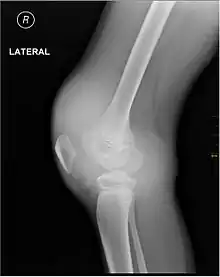

X-ray of Hemarthrosis